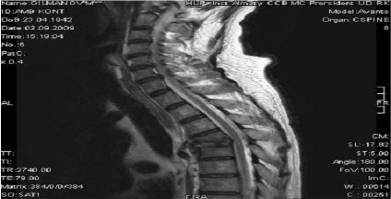

In June 2009 one of the author of

this article Gilmanov Murat was sicken by spinal tuberculosis

On 3th of August 2009 Gilmanov Murat has occurred full paralysis of the bottom part of his body and his legs after distorting of the his forth

and fifth vertebras by tuberculosis infection, as you can see from the photo (fig.2) of the magnetic resonance

tomography from 2nd September of 2009.

Fig.2

The height of the vertebral bodies

decreased, the bone of 4.-5. vertebras

destructed and the space between them is filled with purulence.

Spinal canal is narrowed between 4.-5. vertebras,

with partial spinal cord compression due to epidural abscess till 5 mm.

Conclusion: MRT

data spinal

tuberculosis of 4.-5. vertebras complicated by epidural and paravertebral abscess at this level.